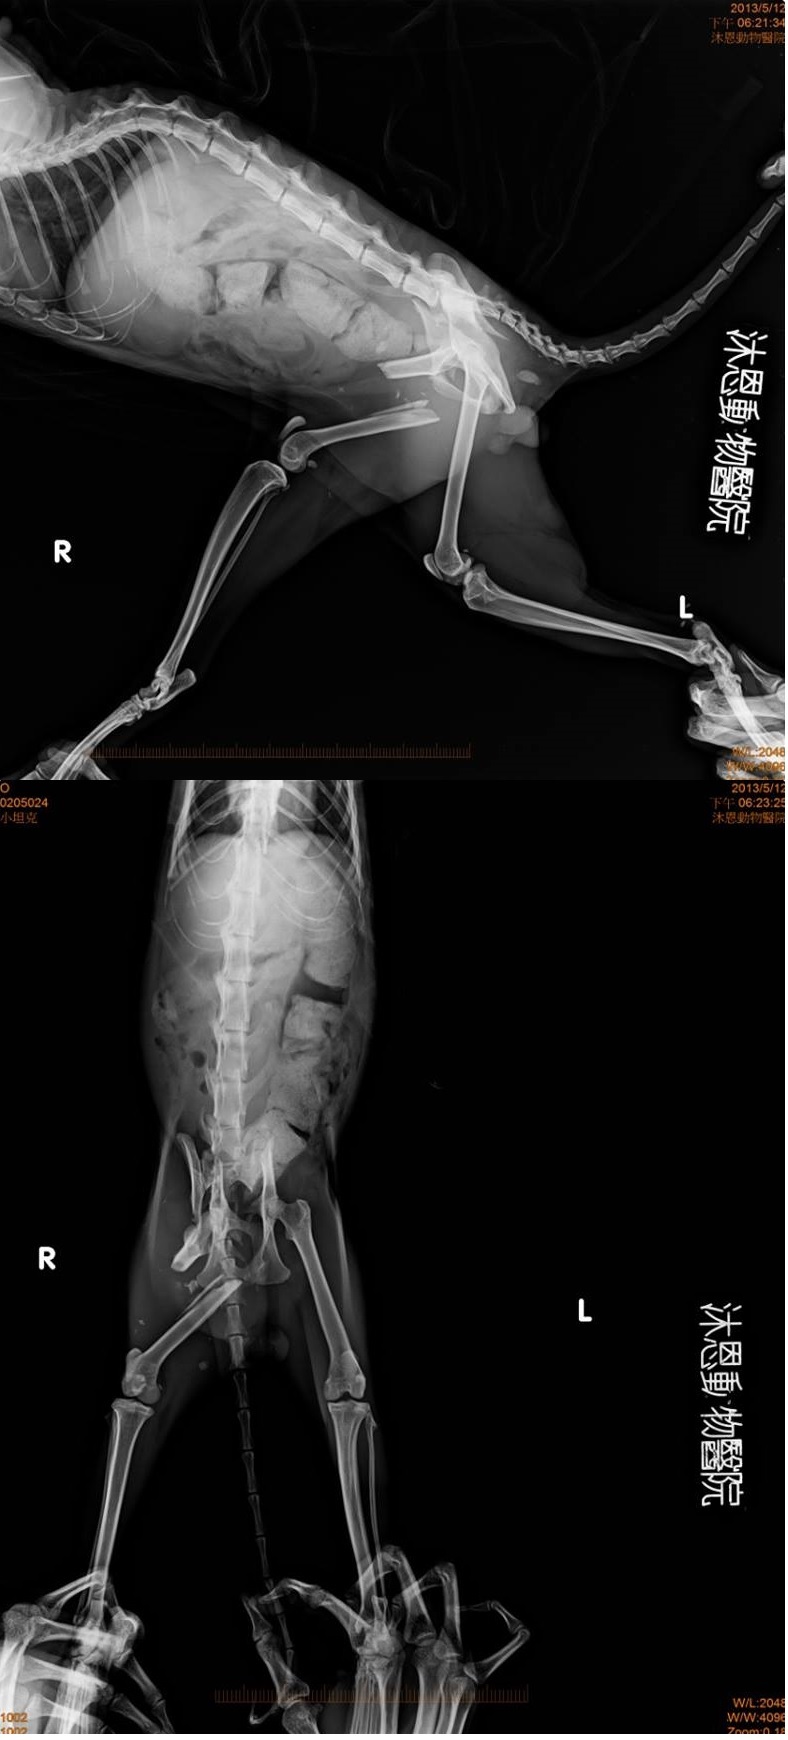

照射是X光片後確認為三處骨折

分別是左腳骨盤、右腳骨盤、右腳大腿

幸運的沒有傷及脊椎

決定僅修復右腳骨盤與右腳大腿